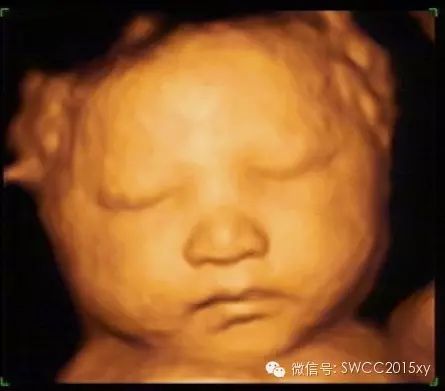

看我皱了一下眉,哦原来我是中国的宝宝,我不是西方的亚当,原来都是妈妈缺钙引起的。因此我们在判断胎儿是否缺钙,不仅仅是看胎儿的长骨的钙化程度和双顶径与股骨的比值,还可以利用现代先进的医学来判断,四维彩超的透明模式来看胎儿的肋骨发育提供更加准确、全面、科学的诊断依据,为减少先天性佝偻病做出应有的贡献。所以准妈妈一定要注意营养、规律、全程、有效补钙哦。